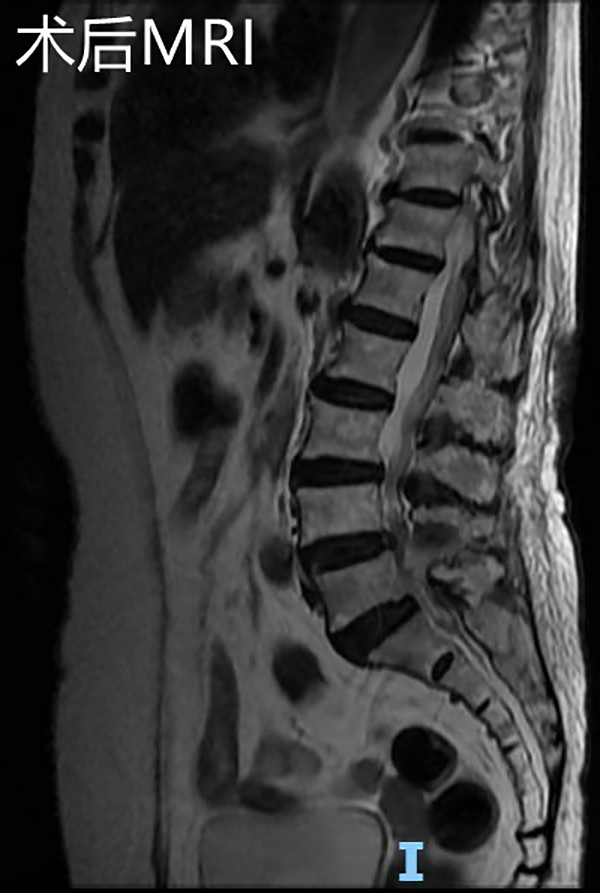

在完善術前檢查,排除手術禁忌,充分做好術前準備后,該手術由微創手術經驗豐富的羅同青副主任醫師主刀。因患者高齡,該手術在局部麻醉+靜脈麻醉下進行,術中麻醉醫師一刻也不敢放松,緊盯監視器屏幕,不斷監測病人的各項生命體征,及時調整藥量,認真配合手術醫生,保證手術順利進行。經過約2小時,成功解除了患者的腰椎管狹窄及神經根壓迫,術中出血約10ml,手術順利,沒有出現神經損傷等并發癥。

手術后復查腰椎MRI顯示:相應的椎管狹窄及神經根壓迫已解除,手術后第2天邱奶奶便可下地行走,腰痛及左下肢疼痛緩解,復查腰椎磁共振見L4/5左側狹窄已完全解除。手術后第4天,患者順利出院,沒有出現任何手術并發癥。